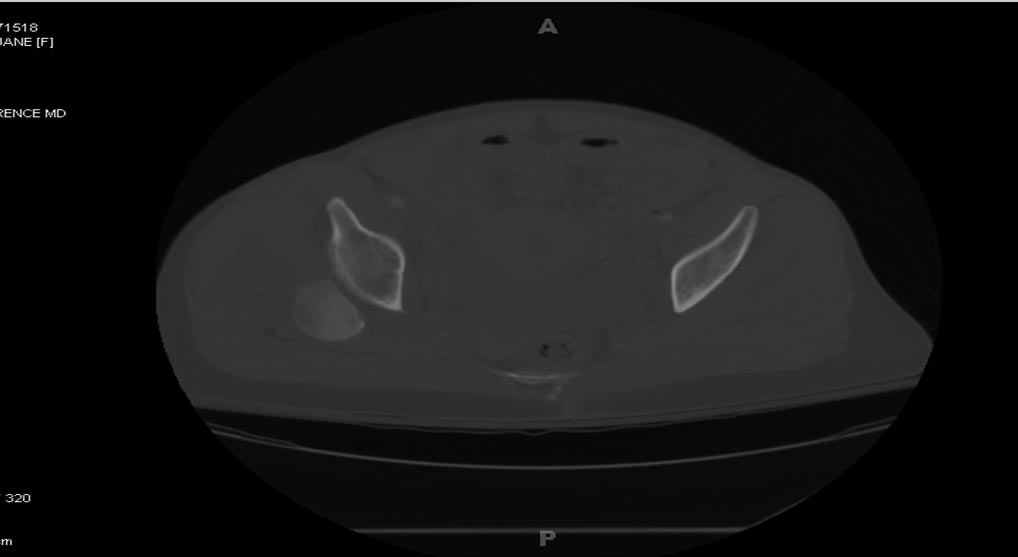

На 25 день с момента травмы операция на Jackson table с боковым обширным доступом. Удаление стержней с местной обработкой. В тазобедренном суставе удаление головки, на дне вертлужной впадины полная отслойка хряща. Вертлужный компонент с одним винтом и короткая ножка - Fitmore press fit stem. На второй день однократно доза радиации для профилактики гетеретопической оссификации. Послеоперационный период без температуры. Выписана. Нагрузку разрешили на левой стороне, а полная в 3 мес. Здесь снимки при амбулаторном наблюдении: послеоперационно, 2 мес, 3 мес и 6 мес. Нагрузка полная, отсутствует хромота, и нет жалоб.